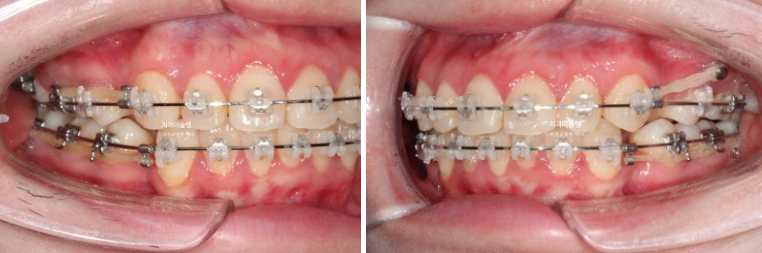

치료시작 10개월차 모습입니다.

가위교합의 원활한 개선을 위해서는 매복 사랑니 발치가 필요하여 사랑니 발치도 하셨습니다.

24.06

발치공간을 닫으며 앞니를 뒤로 움직이는 중입니다.

가위교합의 개선을 위해서는 입천장에 교정용 나사가 필요합니다.

앞니를 최대한 뒤로 많이 넣어야 하는 상황이라서 입천장뿐 아니라 볼쪽에도 교정용 나사를 심고 진행했습니다.